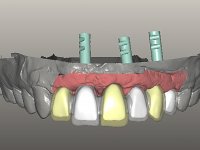

O paciente foi observado conjuntamente e a dúvida que surgiu de imediato foi se seria possível com a regeneração óssea a efectuar poder ser reabilitada naturalmente a zona das papilas interdentárias. Nesse sentido foi feito um enceramento de diagnóstico que contemplaria as duas hipóteses, utilizando ou não a cerâmica gengival. A confecção desse enceramento foi fundamental para expor ao paciente a dificuldade da reabilitação. O wax-up deu origem a um mock-up que foi aprovado pelo paciente e que simultaneamente serviu de guia imagiológica. O caso foi planificado cirurgicamente e realizada uma guia cirúrgica com que foram colocados os implantes. Após 10 semanas foi feita a 1ª impressão para confecção da ponte provisória. Foram criados os primeiros perfis de emergência na gengiva artificial e foi digitalizado o modelo. Por processo de CAD-CAM foi confeccionada uma ponte provisória aparafusada baseada no enceramento de diagnóstico. A ponte trabalhou durante 8 semanas os tecidos moles que foram fielmente copiados numa impressão com técnica de moldeira aberta. Os transferes foram individualizados com resina composta para copiarem fielmente os perfis de emergência criados pela ponte provisória. Confeccionado o modelo de trabalho definitivo, foi realizada uma infra-estrutura em zircónio seguindo a orientação do enceramento de diagnóstico. O assentamento da infra-estrutura foi testado em boca e simultaneamente foi novamente impressionados os tecidos moles com um silicone fluido. Nessa consulta foi feito o levantamento da cor. Os dentes 13 e 23 apresentavam uma saturação anormalmente forte que resolvemos não valorizar, optando por privilegiar a relação com o sector antero-inferior. Foi realizada uma nova gengiva artificial com a impressão que acompanhou a impressão de arrasto com a infra-estrutura. Após a colocação da cerâmica na infra-estrutura foram coladas as meso-estruturas. O trabalho final foi aparafusado lentamente permitindo a adaptação dos tecidos moles.